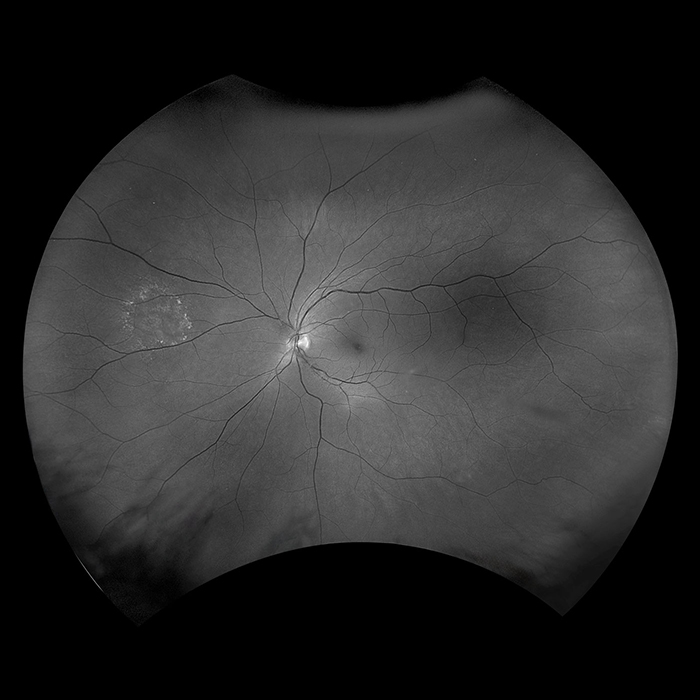

Optos introduced ultra-widefield (UWF™) retinal imaging to enable eyecare professionals to discover, diagnose, document and treat ocular pathology that may first present in the periphery - pathology which may go undetected using traditional examination techniques and equipment. Our UWF, high-resolution retinal imaging devices each image more than 80% or 200˚ of the retina in a single shot. Our complete list of ultra-widefield retinal imaging devices is below.

California was developed for medical imaging and is a standard for retinal screening programs. California is available in multiple models with multiple imaging modality options. California produces a 200°, single shot retinal image of unrivaled clarity in less than ½ second and is changing the management of diseases including Geographic Atrophy, Diabetic Retinopathy, AMD, and Uveitis.

Daytona produces a 200° single shot optomap retinal image of unrivaled clarity in less than ½ second. This fast, easy, patient-friendly, ultra-widefield imaging technology was designed for healthy eye screening and has been shown to improve practice flow and patient engagement.